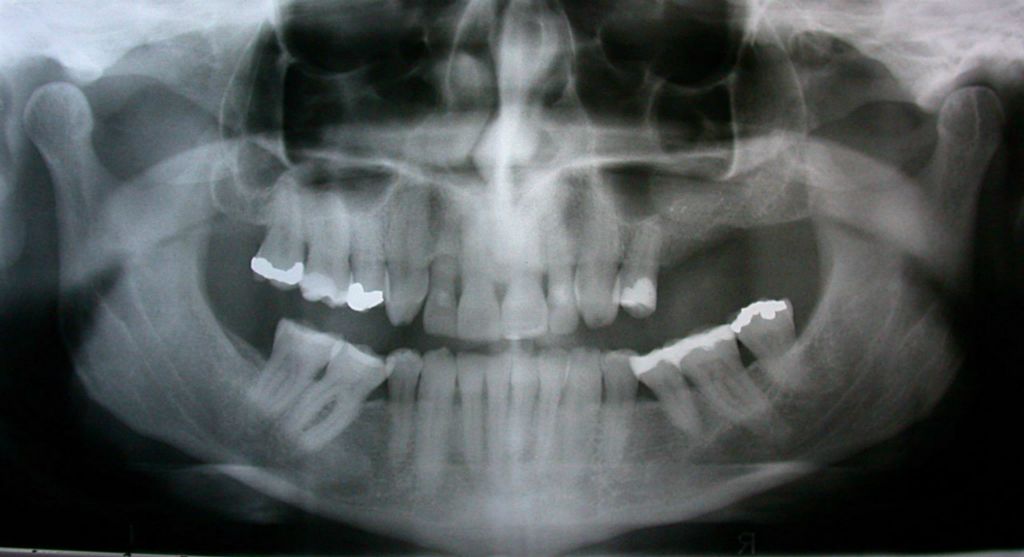

Before

After

Dental Bridge

Partial denture with precision attachments